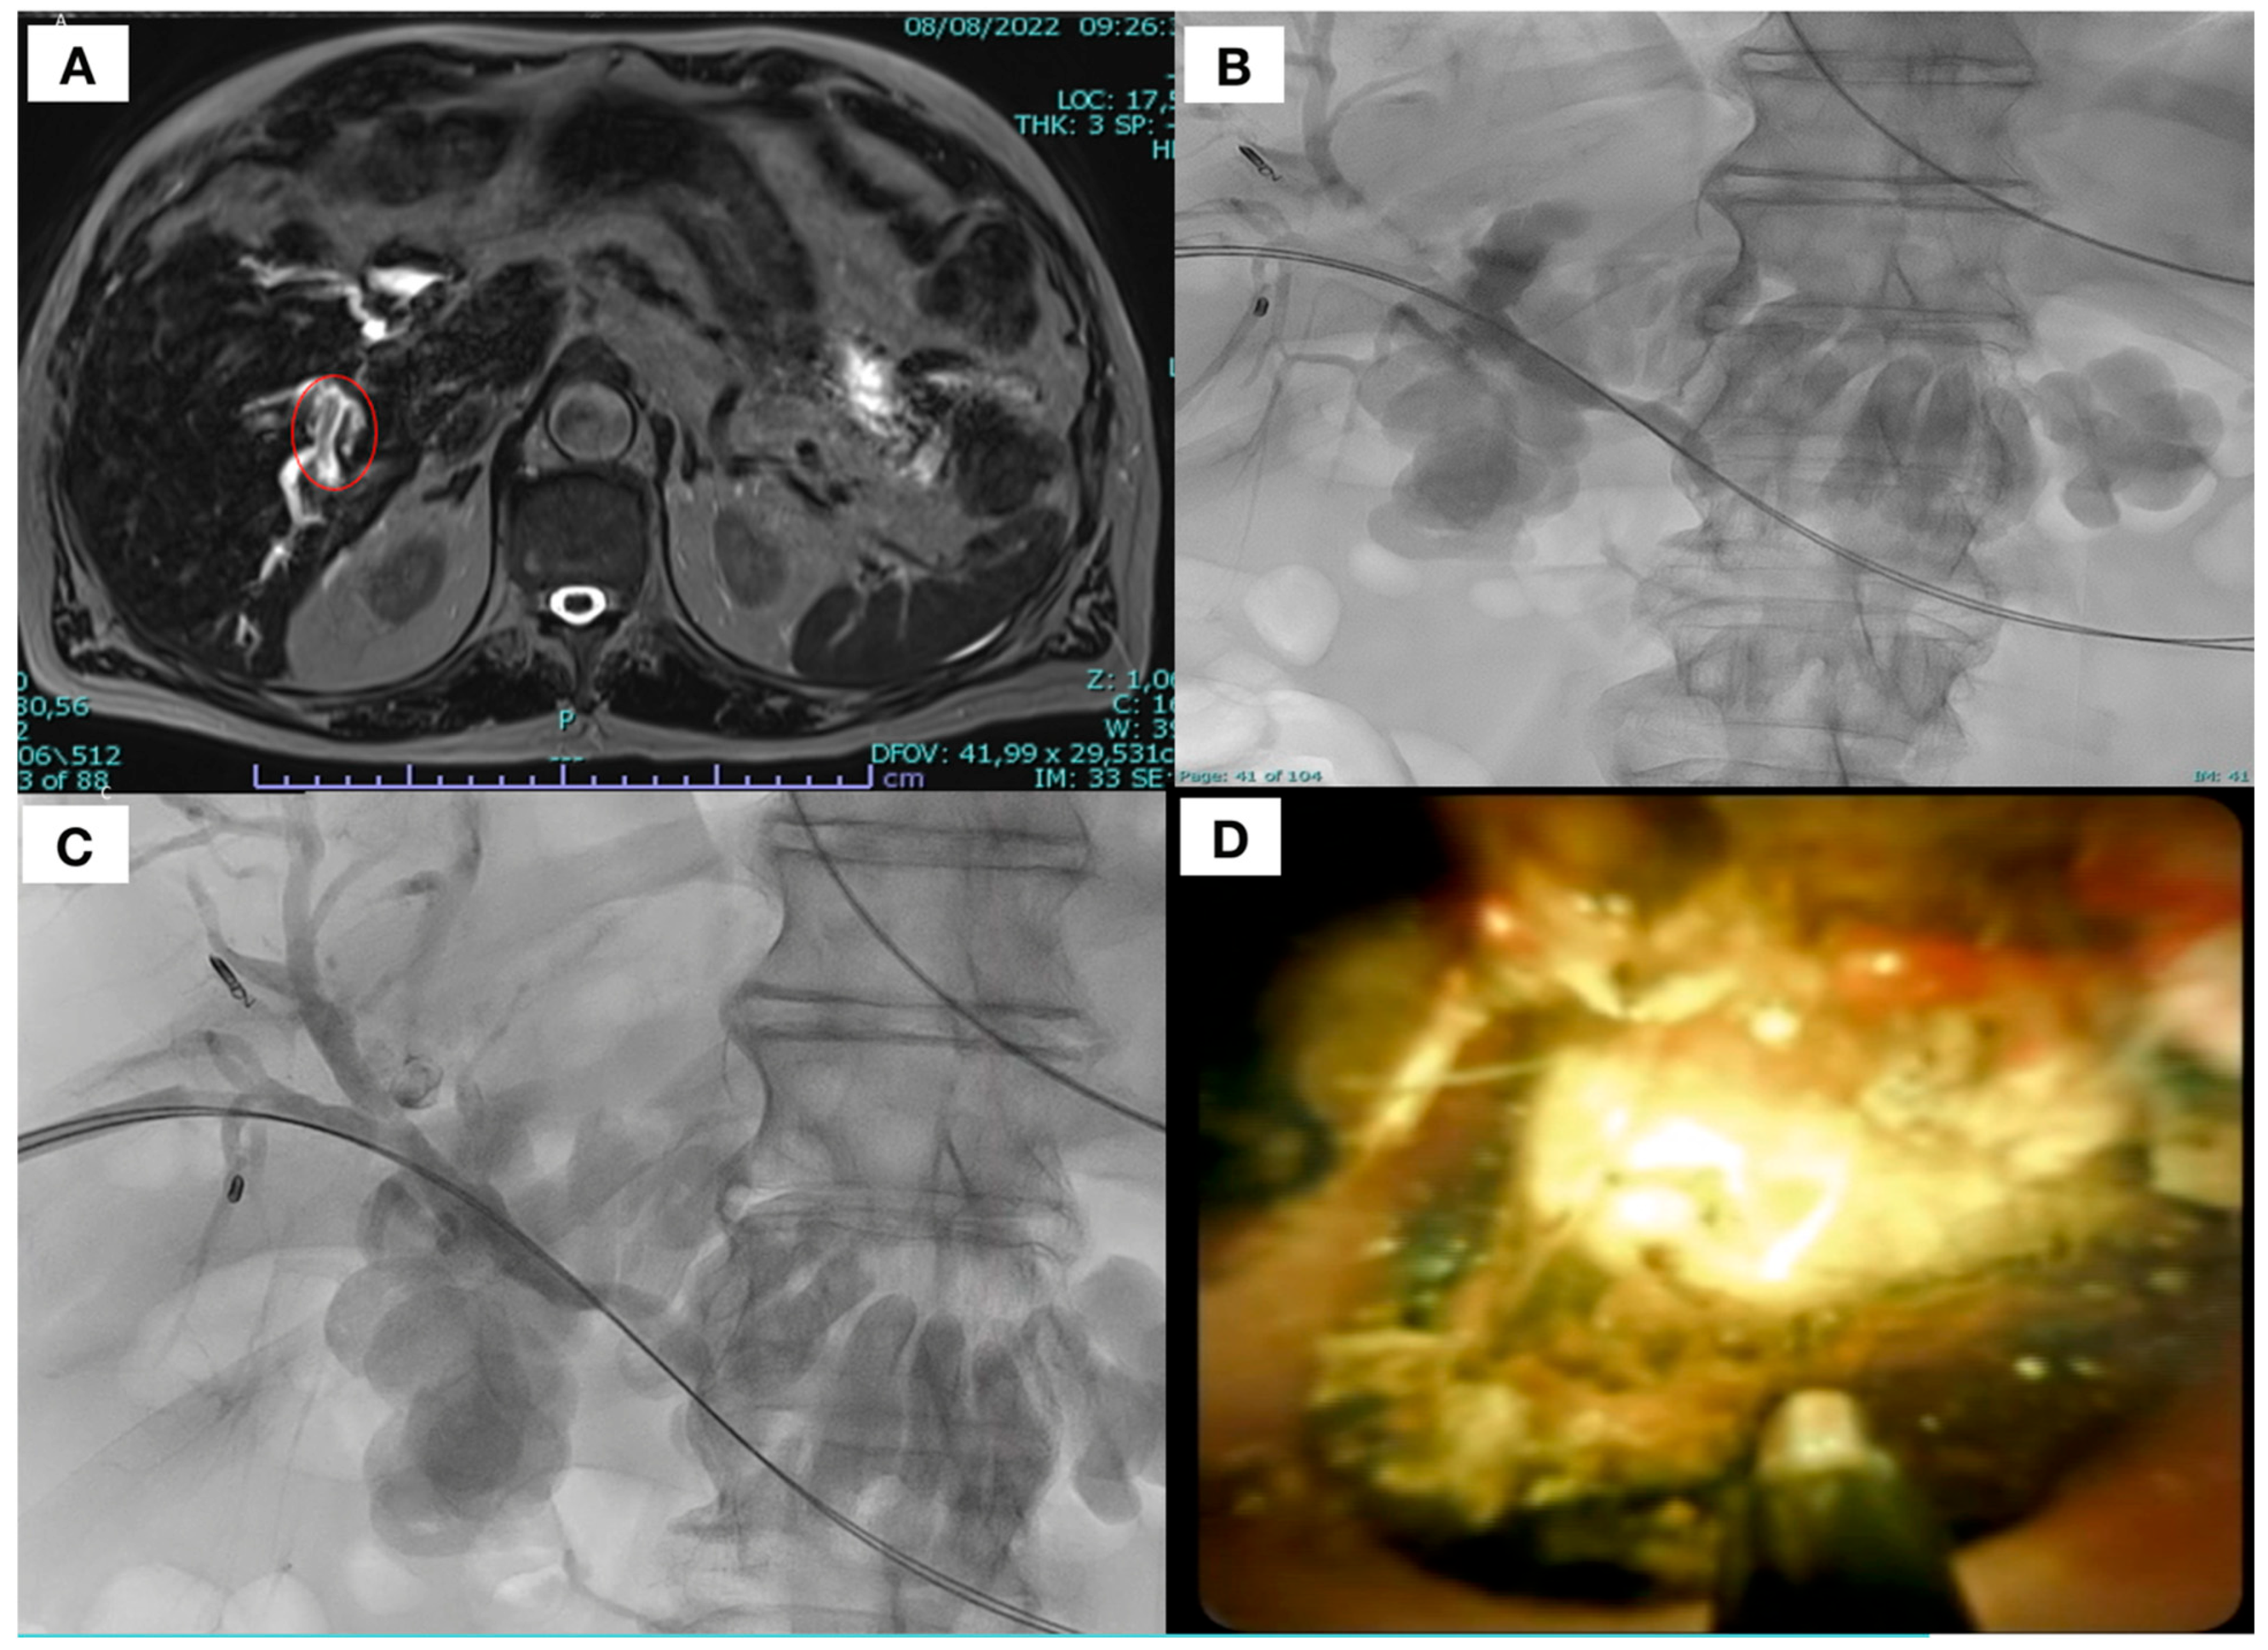

2.5. Procedure